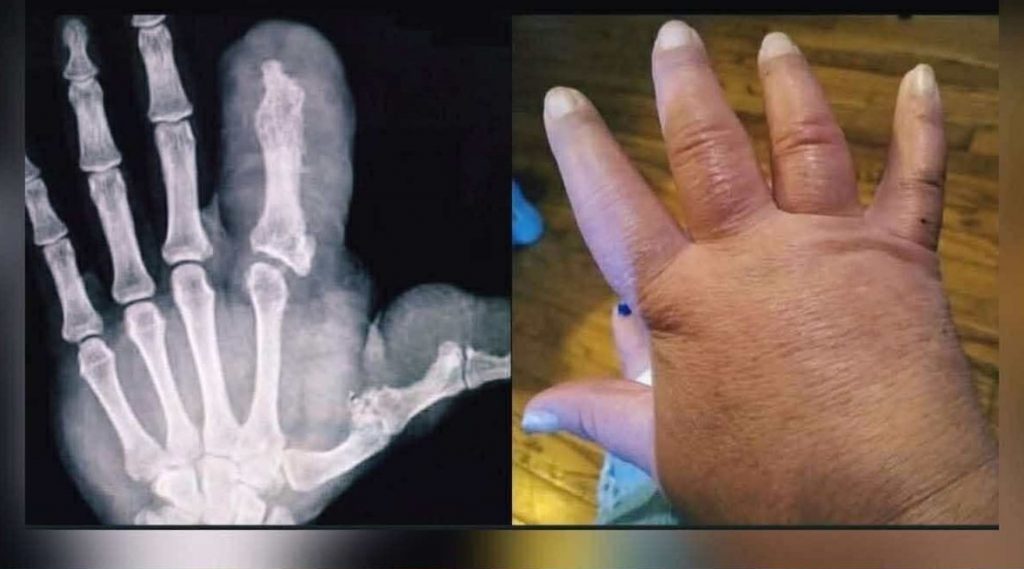

Depuis sa naissance, son pouce avait grandi plus vite que le reste de sa main. Au début, cela paraissait anodin, une petite bizarrerie d’enfance dont on parlait avec le sourire. Mais année après année, la peau se tendit, l’ongle devint comme une petite coquille, et la main perdit sa forme familière. Les médecins attribuèrent ce phénomène à un mot qui semblait presque étranger : macrodactylie. Cela expliquait tout et rien à la fois.

Quand on lui a proposé l’opération, sa mère tremblait plus que sa fille. « On va juste ralentir un peu la croissance, d’accord ? » dit doucement le médecin, comme s’il expliquait quelque chose à une fleur vivante. Après l’anesthésie, il y eut la douleur, une sensation de brûlure, puis des bandages comme un cocon, et un espoir discret : peut-être que maintenant tout allait s’arrêter. Mais le doigt recommença à pousser.